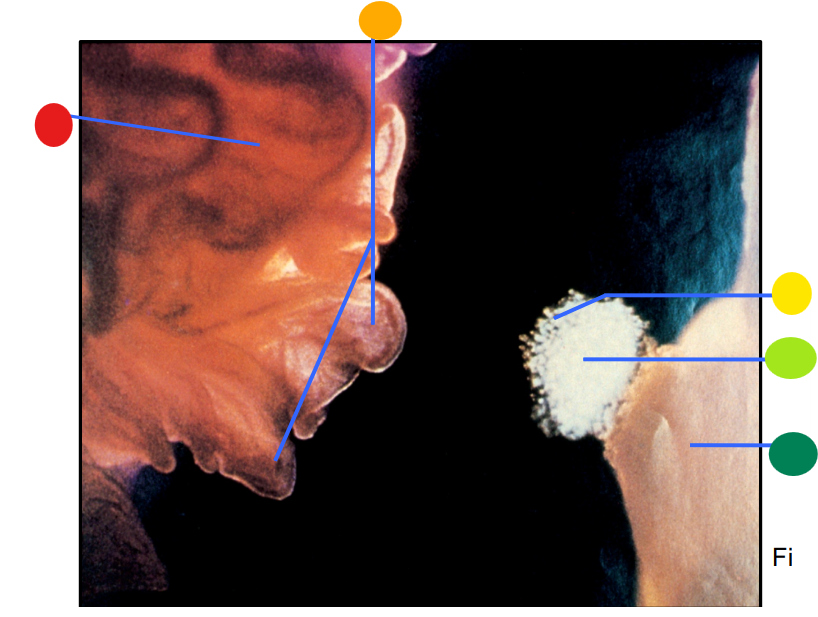

red

infundibulum

orange

fimbriae

yellow

cumulus oophorus

light green

oocyte

dark green

ovary

How is the egg and culmulus oophorus drawn into the infundibulum after the rupture of a mature follicle?

via ciliary action